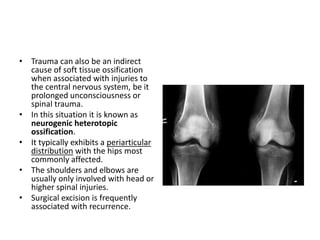

• Trauma can also be an indirect

cause of soft tissue ossification

when associated with injuries to

the central nervous system, be it

prolonged unconsciousness or

spinal trauma.

• In this situation it is known as

neurogenic heterotopic

ossification.

• It typically exhibits a periarticular

distribution with the hips most

commonly affected.

• The shoulders and elbows are

usually only involved with head or

higher spinal injuries.

• Surgical excision is frequently

associated with recurrence.